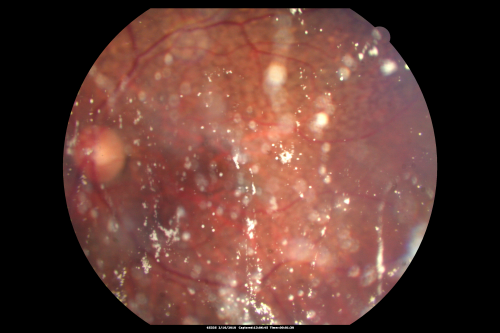

80 year old woman with Reticular Drusen (pseudodrusen) 20/30 Vision - Before Vitrectomy

80 year old woman with asteroid hyalosis and macular degeneration.

OPHTHALMIC EXAMINATION: Visual acuity with correction 20/30-3 OD and 20/30-2